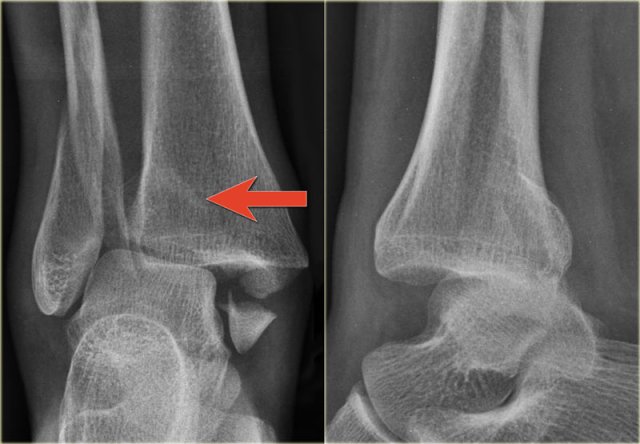

The images show an obvious Weber B fracture.

On the AP-view the linear lucency is the clue to a tertius fracture (red arrow).

It results from subtle malalignment of the fracture fragment.

Likewise in some cases malalignment can result in a linear density.